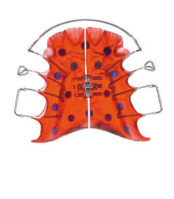

Die erste Zahnspange

Falls notwendig, werden neue Abdrücke genommen, um ein Gerät anfertigen zu können, oder es wird schon ein neues Gerät eingesetzt.

Ab jetzt spricht man von einer laufenden Behandlung. Alle 4-6 Wochen (je nach Gerät und Entwicklungsstadium) finden Kontrolltermine in der Praxis statt, um die Wirkung der Geräte zu überprüfen.